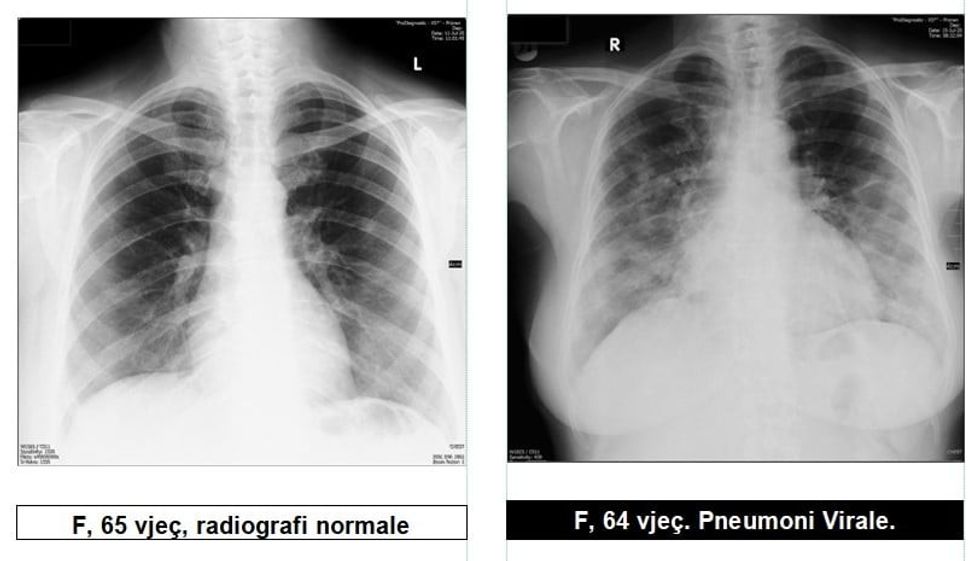

Radiologu Krasniqi tregon pamjet e mushkërive të pacientëve me COVID-19: Virus ka, pandemi ka dhe situata nuk është e mirë

Radiologu në Spitalin Rajonal të Prizrenit, Sylejman Krasniqi tregon pamjet e mushkërive të pacientëve me pneumoni virale.

“Për te gjithë ata që maskat i kane veç si dekorim, për ata që distancën sociale e kanë diçka të huaj dhe për të gjithë ata që nuk i respektojnë këshillat e institucioneve relevante Shëndetësore, këto imazhe le të ju shërbejnë që ta kuptoni se megjithatë virus ka, pandemi ka dhe situata nuk është e mirë”, ka shkruar Krasniqi, përcjell Telegrafi.